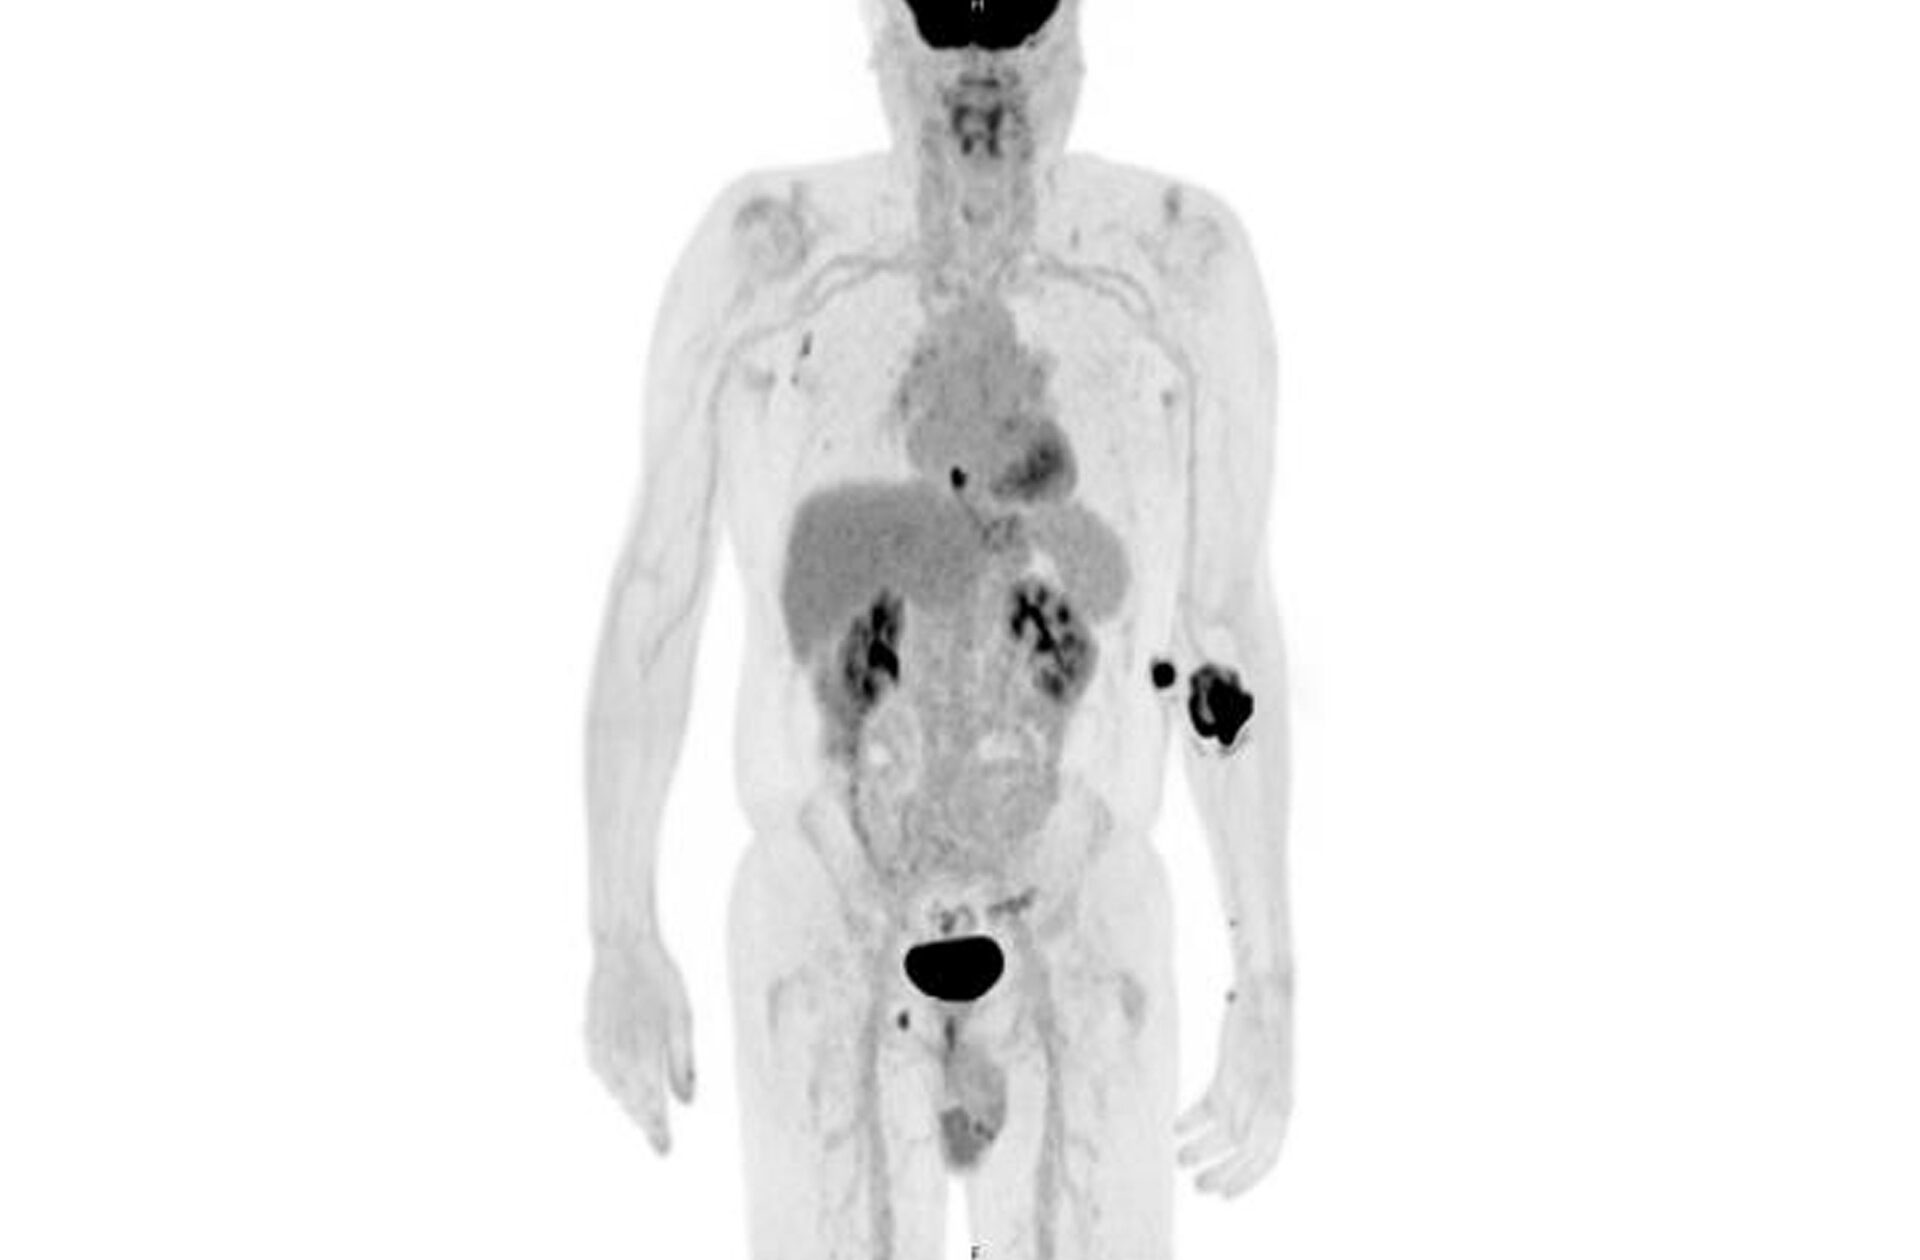

FDG Uptake

PET/CT showing FDG uptake at the distal esophagus, consistent with malignancy. There is also FDG uptake at the gastroesophageal junction, likely inflammatory or physiologic, along with FDG-avid bilateral hilar foci, right axillary nodes, and a right inguinal node—findings most consistent with inflammation. Source: NYU Langone Health